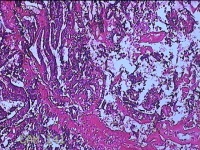

性别

女

年龄

34岁

临床诊断

异常子宫出血

一般病史

阴道不规则流血1月余。

标本名称

宫内物

大体所见

灰白暗红色不规则碎组织4.8x4.3x1.3cm一堆。

单纯性增生,局部呈复杂型增生